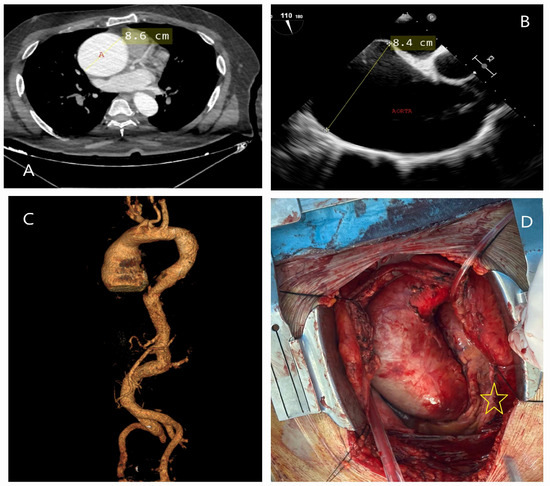

5.2.3. Computed Tomography